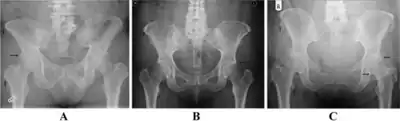

Enthesophytes are abnormal bony projections at the attachment of a tendon or ligament.[1] They are not to be confused with osteophytes, which are abnormal bony projections in joint spaces. Enthesophytes and osteophytes are bone responses for stress.[1]